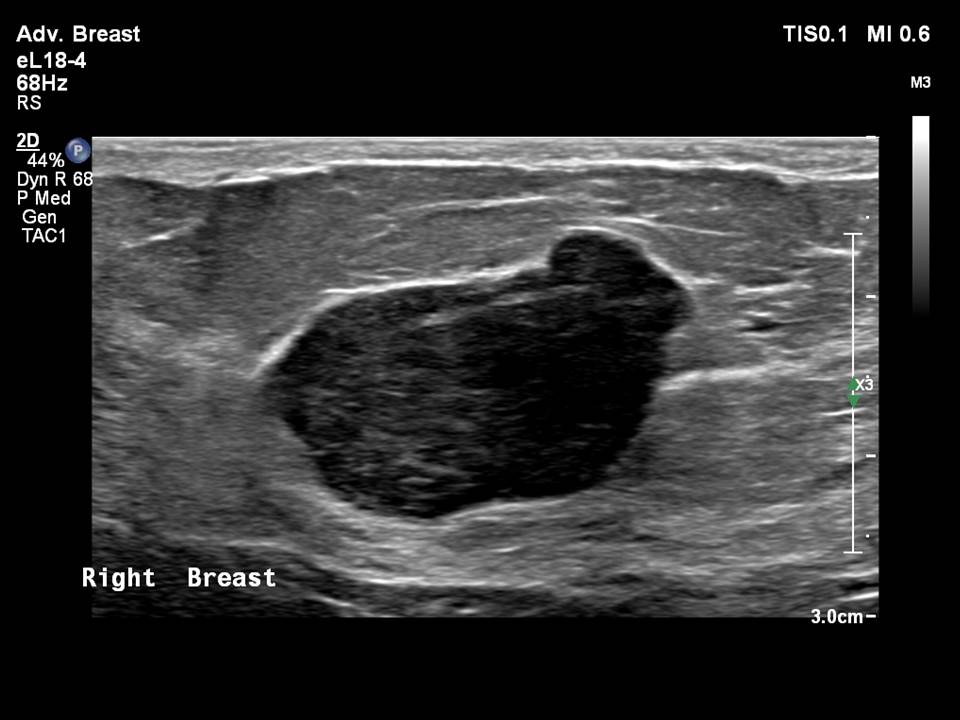

Breast Ultrasound cancer 1 YouTube What Does Shadowing Mean On Breast Ultrasound When silicone leaks out of the implant it will cause a. 30% multiple projections from the nodule within or around ducts. This loss is displayed in the image as. Sometimes this lobulation can give the impression of a lump in the breast (figure). As ultrasonic beams propagate through tissues, there is a loss of energy by absorption, reflection and scattering.. What Does Shadowing Mean On Breast Ultrasound.

Right breast ultrasound demonstrates an irregular shaped, hypoechoic What Does Shadowing Mean On Breast Ultrasound When silicone leaks out of the implant it will cause a. As ultrasonic beams propagate through tissues, there is a loss of energy by absorption, reflection and scattering. 30% multiple projections from the nodule within or around ducts. Acoustic shadowing occurs when an ultrasound beam encounters a highly reflective or dense structure within the body. Collections or silicone leakage **.. What Does Shadowing Mean On Breast Ultrasound.